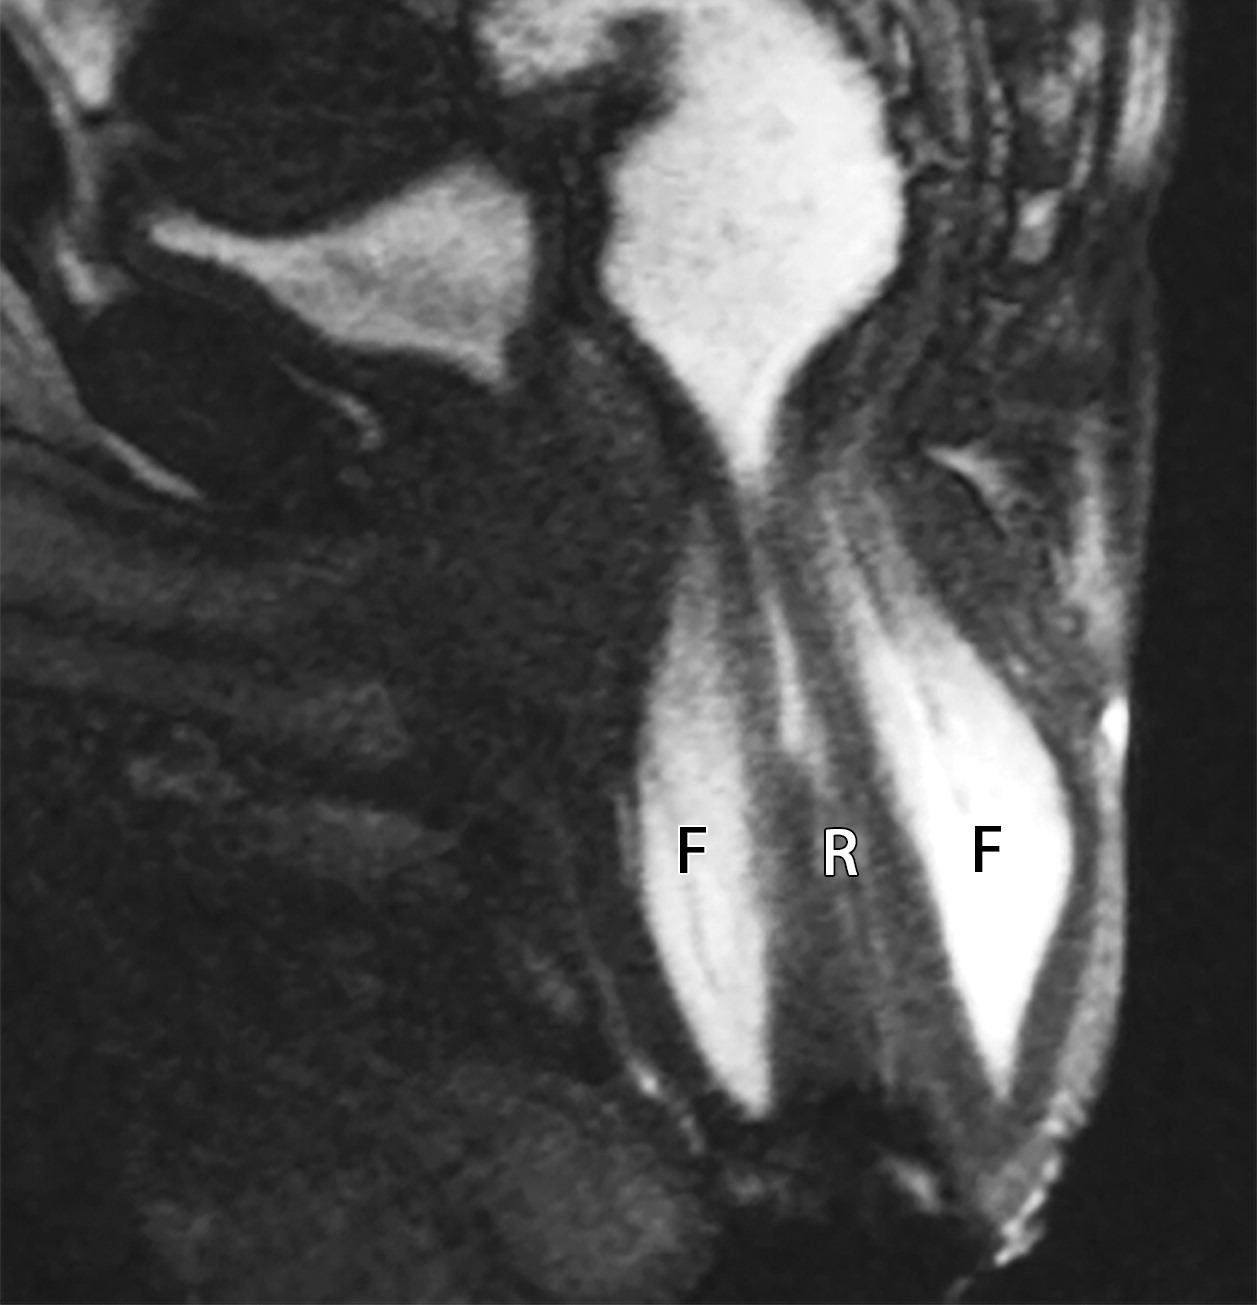

5b37c973dc3130b025d5647c71540da5.jpeg279c20ad5aa41e2c495e2183e2cf526d.jpeg

直肠脱垂。

(a图)为静息态,(b图)为增加腹压态。可见直肠(白色字母R)及轴位的腹膜脂肪(黑色字母F)在增加腹压时全层脱垂。